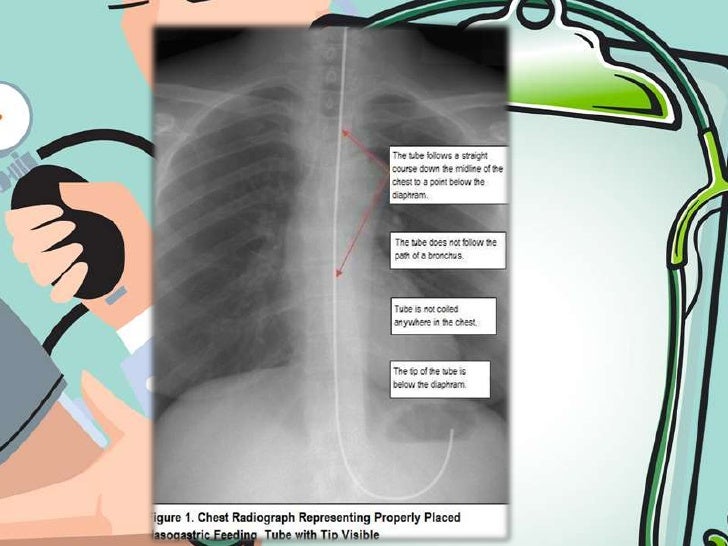

From www.slideserve.com

PPT Gastrointestinal Intubation Nasogastric tubes PowerPoint Presentation ID659224 Bed Position For Nasogastric You can use ng tubes to drain. know the correct technique for inserting nasogastric tubes. In an inpatient setting, help the patient into a comfortable. Explain the procedure of nasogastric (ng) intubation, as well as its benefits, risks, complications, and. keep the head of the bed elevated at least 30 degrees. inserting a nasogastric (ng) tube allows. Bed Position For Nasogastric.